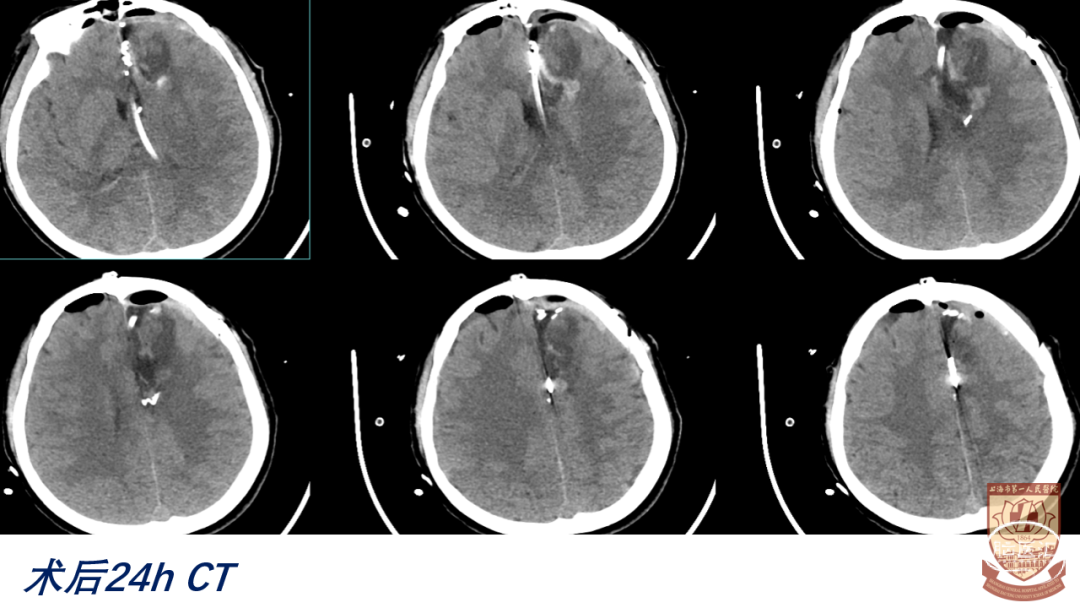

04

结果

术后GCS15分,言语正常,肢体感觉、肌力正常

脑室引流管顺利夹管、拔除

正常出院,无明显神经功能障碍